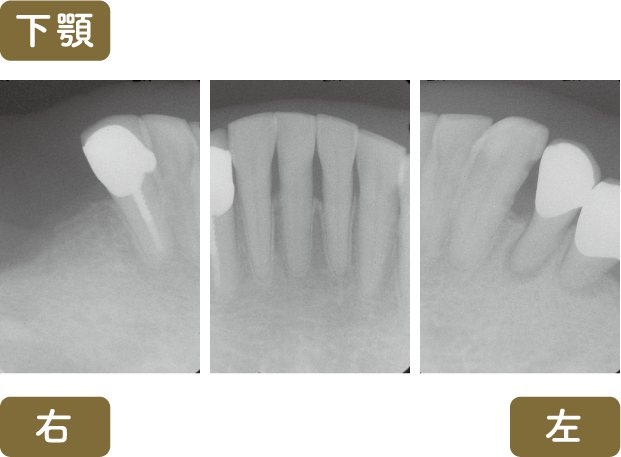

■術後レントゲン写真

は再根管治療を行いました

根の先まで根管充填されている事がわかると思います

根管充填はMTAを使用しています